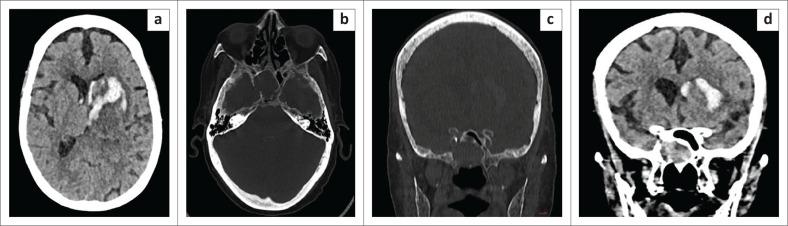

Intrasphenoidal encephalocoeles are acquired or congenital herniations of meninges and brain parenchyma through a structural sphenoid bone defect. Acquired causes are most common, either iatrogenic, post-traumatic, or spontaneous. However, defects in the lateral wall of the sphenoid sinus are uncommon and cephalocoeles through them relatively underexplored in current literature, warranting dedicated attention to unravel their complexities. Congenital causes such as persistence of Sternberg's canal, which can lead to lateral cephalocoeles, is a rare entity, seen in two of the presented cases, based on the location of the defect with respect to the line connecting the foramen rotundum and the vidian canal (VR line). Three cases of intrasphenoidal cephalocoeles are presented; two patients presented with watery nasal discharge without prior trauma or surgery and the third case was incidentally detected in an elderly patient with intraparenchymal haemorrhage. Imaging with CT cisternography and brain MR were performed to ascertain the exact location of the leak and confirm the presence of herniated brain tissue via the defects. Patients were evaluated by otolaryngology for transnasal endoscopic repair, which was deemed unfeasible, and referred to neurosurgery for transcranial duroplasty.

蝶窦内脑膨出是指脑膜和脑实质通过蝶骨结构缺损形成的后天性或先天性疝出。后天性病因最为常见,包括医源性、创伤后或自发性病因。然而,蝶窦外侧壁缺损并不常见,目前文献中对通过这些缺损形成的脑膨出研究相对较少,因此需要专门关注以揭示其复杂性。先天性病因如施特恩贝格管持续存在可导致外侧脑膨出,这是一种罕见情况,在所呈现的两例病例中可见,其依据缺损相对于连接圆孔和翼管的线(VR线)的位置而定。本文呈现了三例蝶窦内脑膨出病例;两例患者表现为水样鼻溢液,无既往创伤或手术史,第三例在一名老年脑实质内出血患者中偶然发现。进行了CT脑池造影和脑部磁共振成像以确定漏口的确切位置,并通过缺损确认疝出脑组织的存在。患者接受了耳鼻喉科评估以进行经鼻内镜修复,但认为不可行,随后转诊至神经外科进行经颅硬脑膜成形术。